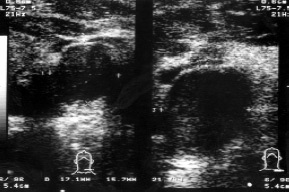

Amikor ultrahang retrosternalis nyirokcsomók keresztül nadklyuchichnvy hozzáférési jogot talált több patológiásán elváltozott nyirokcsomó mérete 5 mm 12,4x14,3 és 22,3x15,4 mm (3. ábra). Más csoportok nyirokcsomók felületét helyen (hónaljban és kulcscsont alatti) nem válnak láthatóvá, ami arra utal, hogy a hiánya rosszindulatú. A folyamat során az ultrahang egy beszélgetés során a beteg kiderül, hogy közben a 3 hónapos zavar zsémbes fájdalom az ágyéki, ott is egyfajta diszkomfort, fekvő testhelyzetben. Amikor ultrahang retroperitoneumban 3-5 ágyékcsigolyák konglomerátum észleltünk kórosan módosított aorta nyirokcsomókban 37,9x41,8 mm (ábra. 4). Leírunk a hashártya mögötti nyirokcsomókból értékesítik kapu terület a bal vese helyét, hogy zavart a vizelet kiáramlását (ábra. 5). Echografically kiderült, egy bal oldali hydronephrosist (ábra. 6.).

Ábra. 3. áttétek retrosternalis nyirokcsomók.